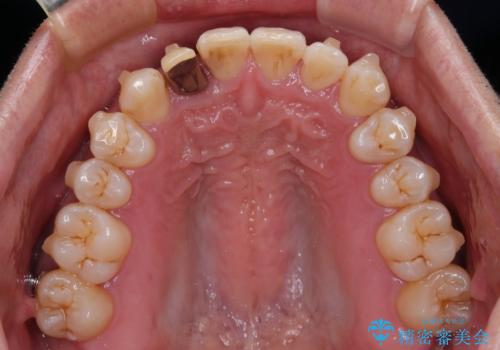

前歯のデコボコを治したい インビザラインによる矯正治療

- 前歯のデコボコを気にして来院された患者様です。

目立たない装置で手軽に治したいとのことで、インビザラインにて矯正治療を行うこととしました。

前歯のクラウンは変色が著しいため、矯正治療後にオールセラミッククラウンにて補綴治療を行うこととしました。